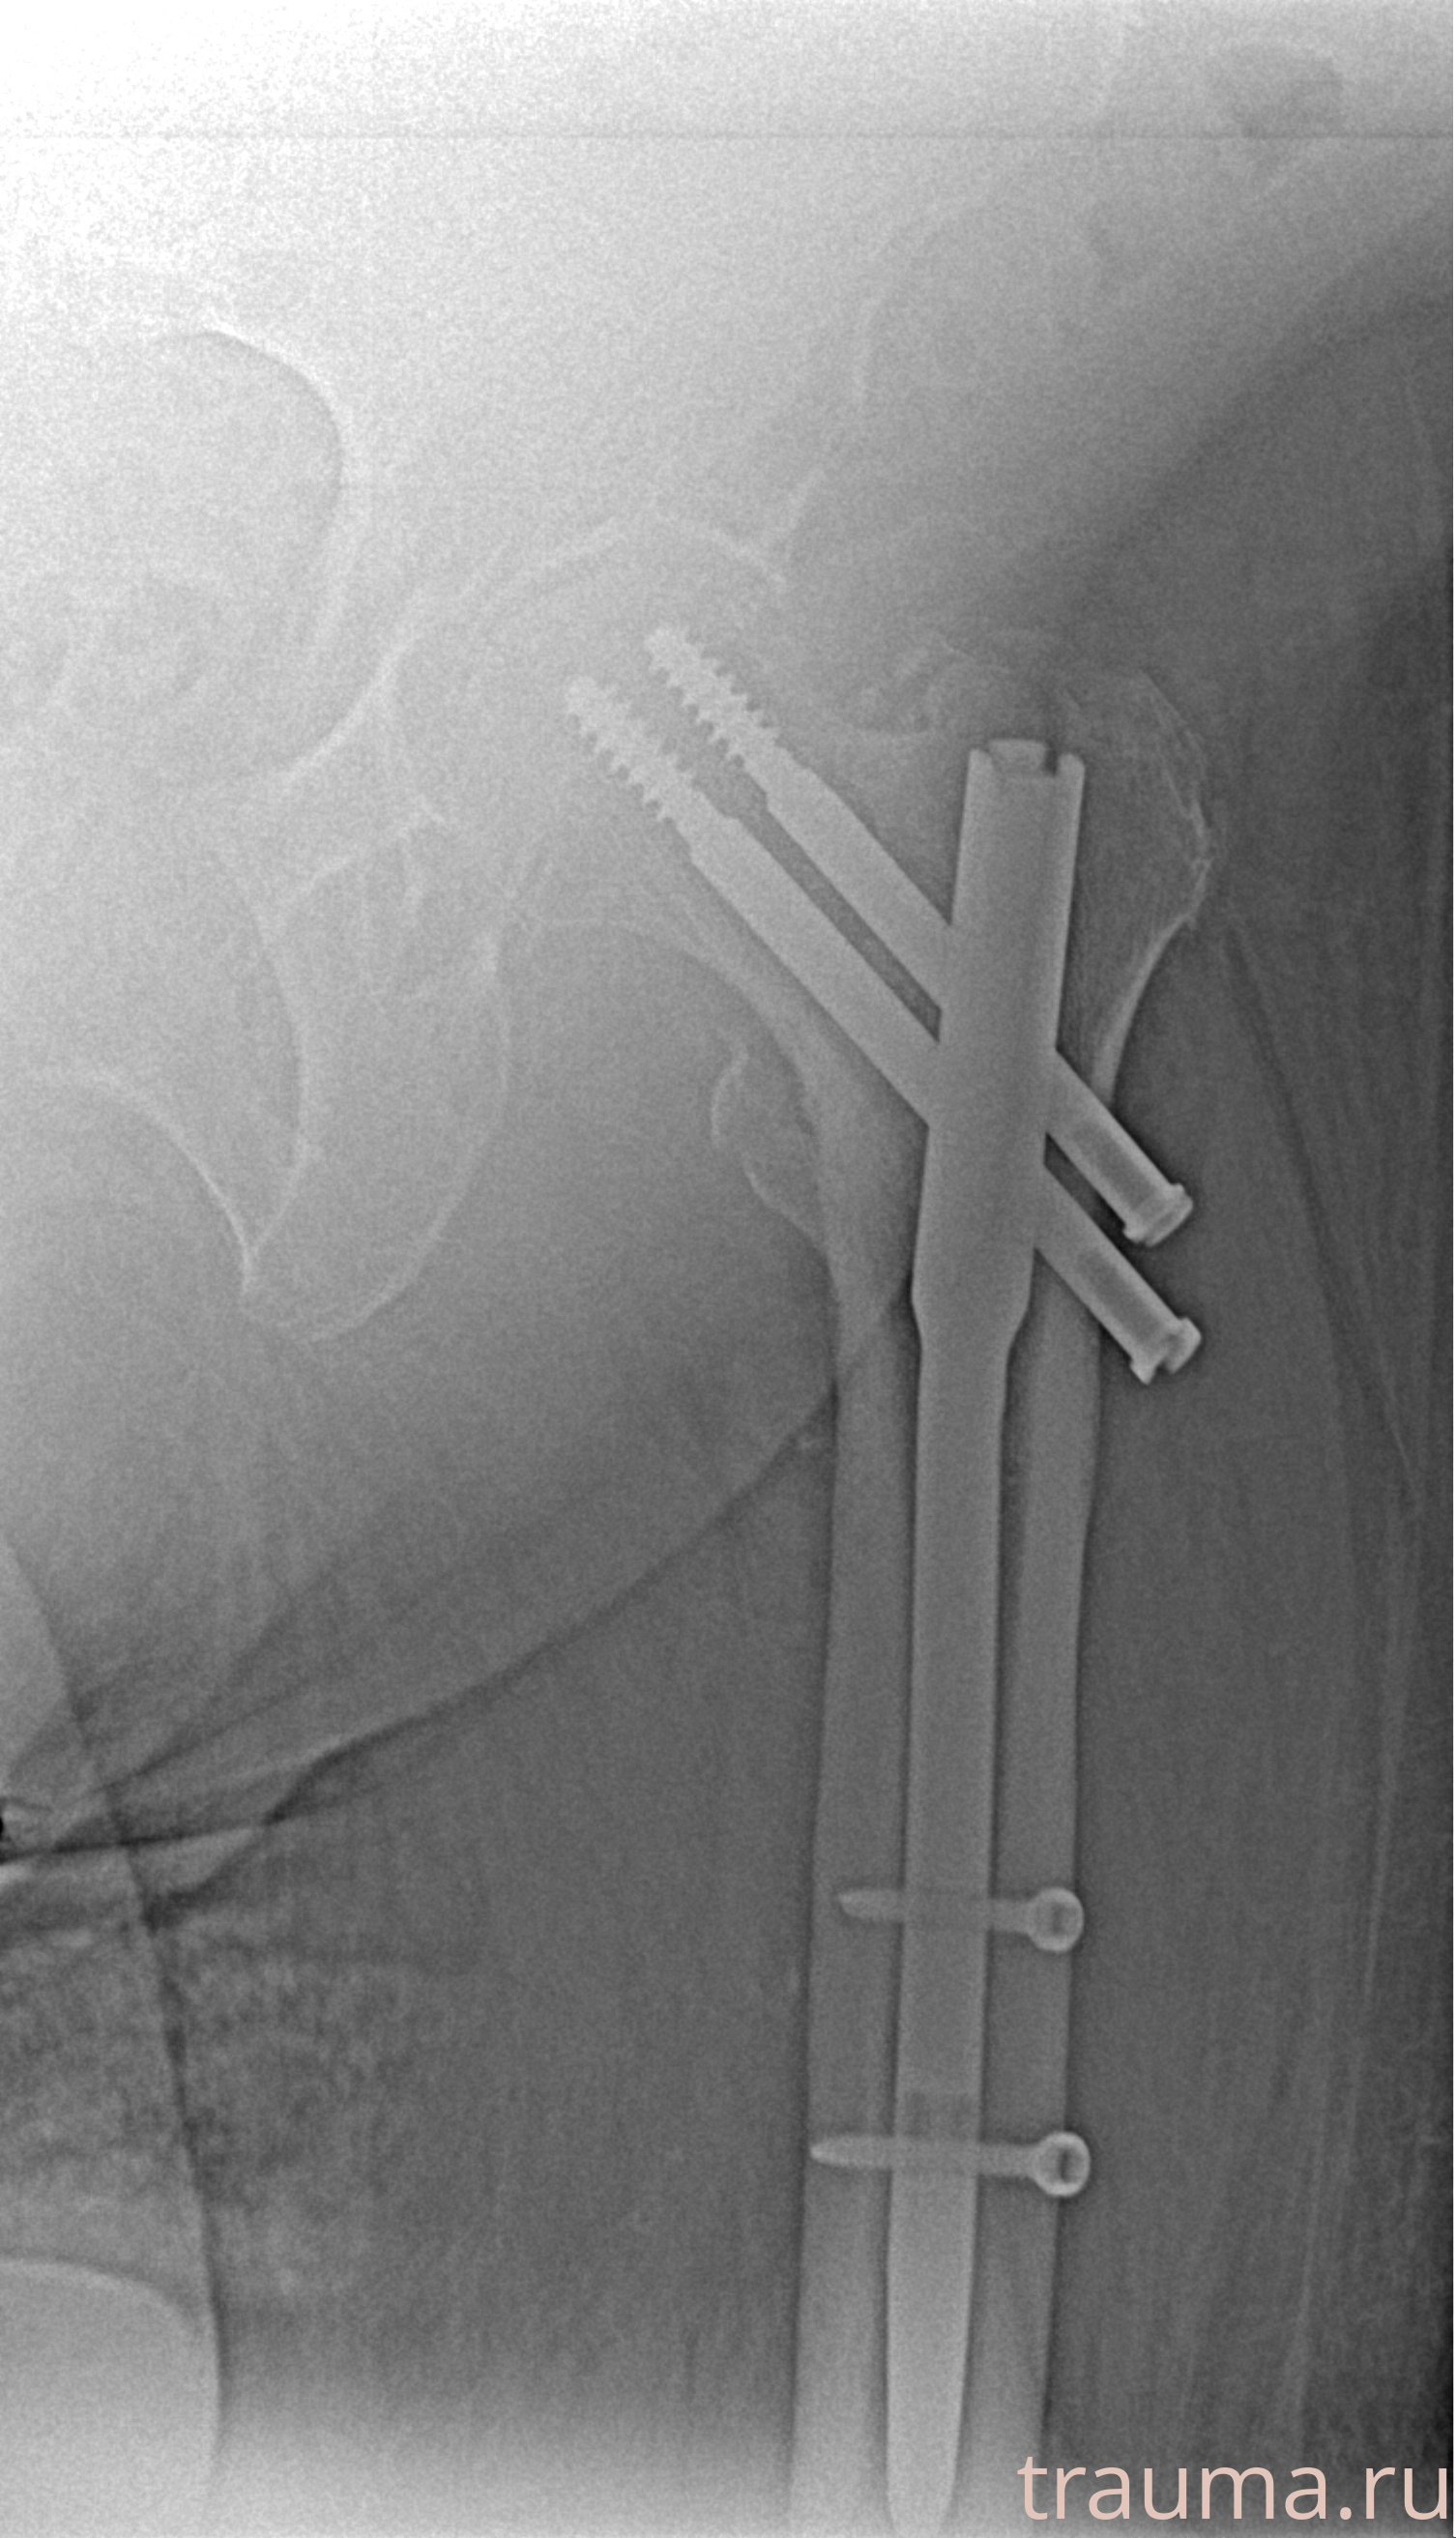

Рентгенограммы

Рентген на дому: по вашему адресу приезжает врач-рентгенолог, травматолог-ортопед с мобильным рентгеновским аппаратом, проводит диагностику травмы или заболевания, делает необходимые рентгенограммы, дает рекомендации по дальнейшему лечению. Получить качественные снимки в домашних условиях возможно благодаря уникальной методике, разработанной МосРентген Центром для института  Склифосовского